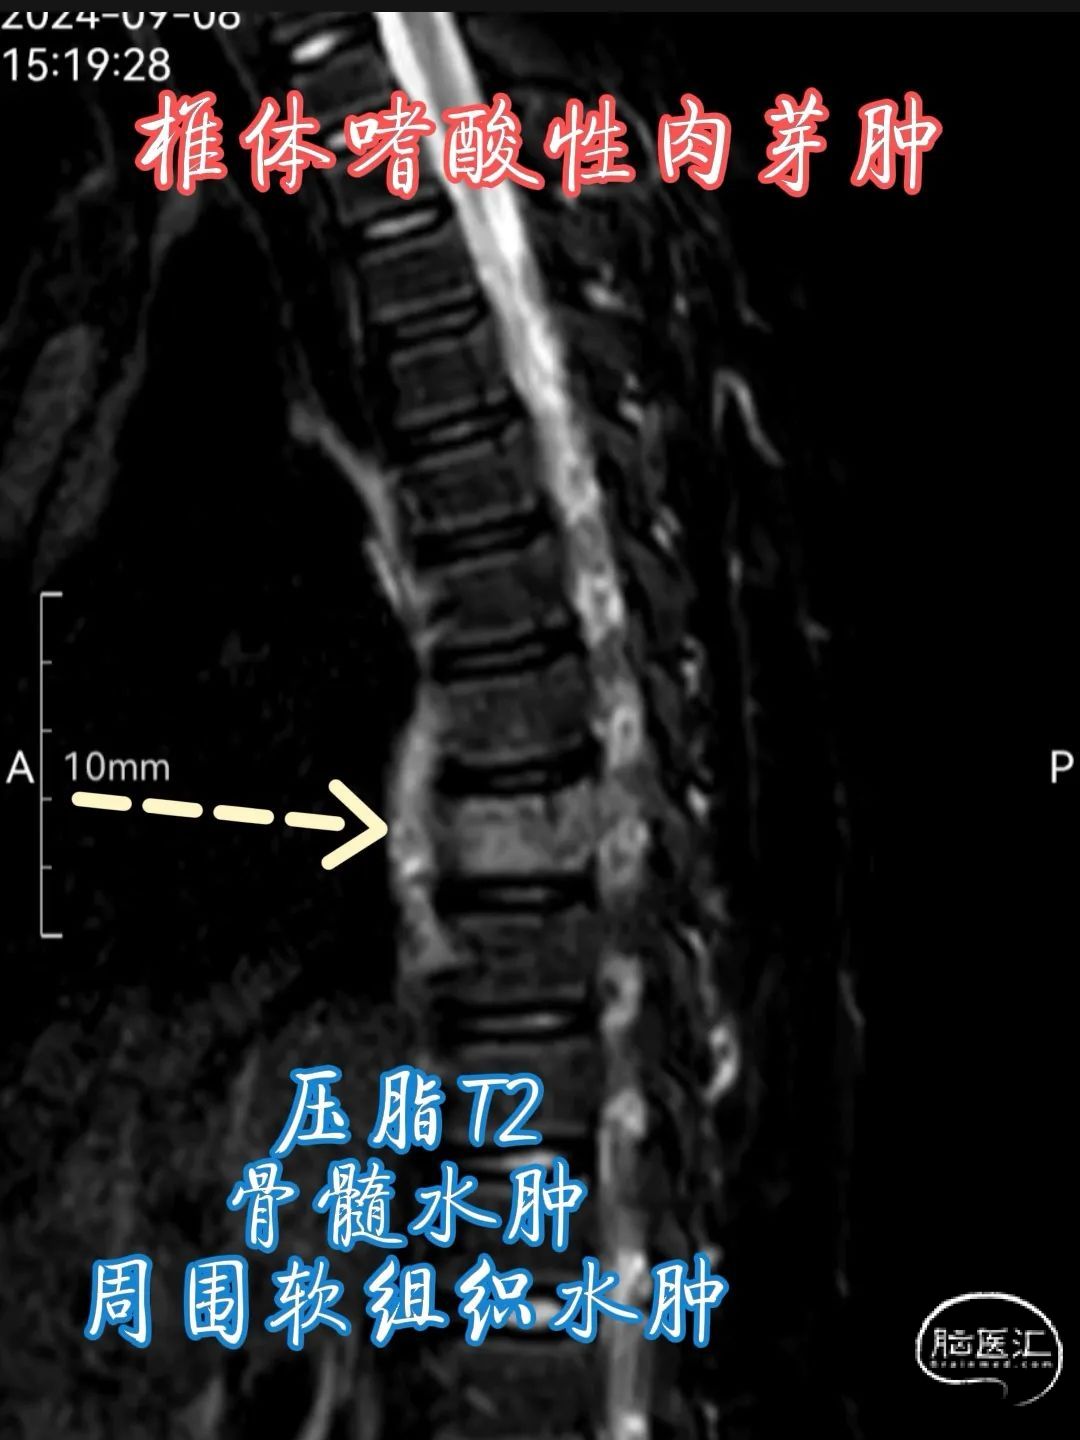

•MRI 检查 :MRI 对于检测椎体嗜酸性肉芽肿具有较高的敏感性,能够清晰地显示病变的范围、部位、形态以及与周围组织的关系。在 T1 加权像上,病变通常呈低到中等信号强度,与正常骨髓相比信号较低;在 T2 加权像上则呈高信号强度,这是由于病变组织内含有较多的水分和黏多糖等成分。此外,MRI 还可显示病变周围的软组织水肿、炎症反应以及神经受压等情况,对于判断病情和制定治疗计划具有重要价值。